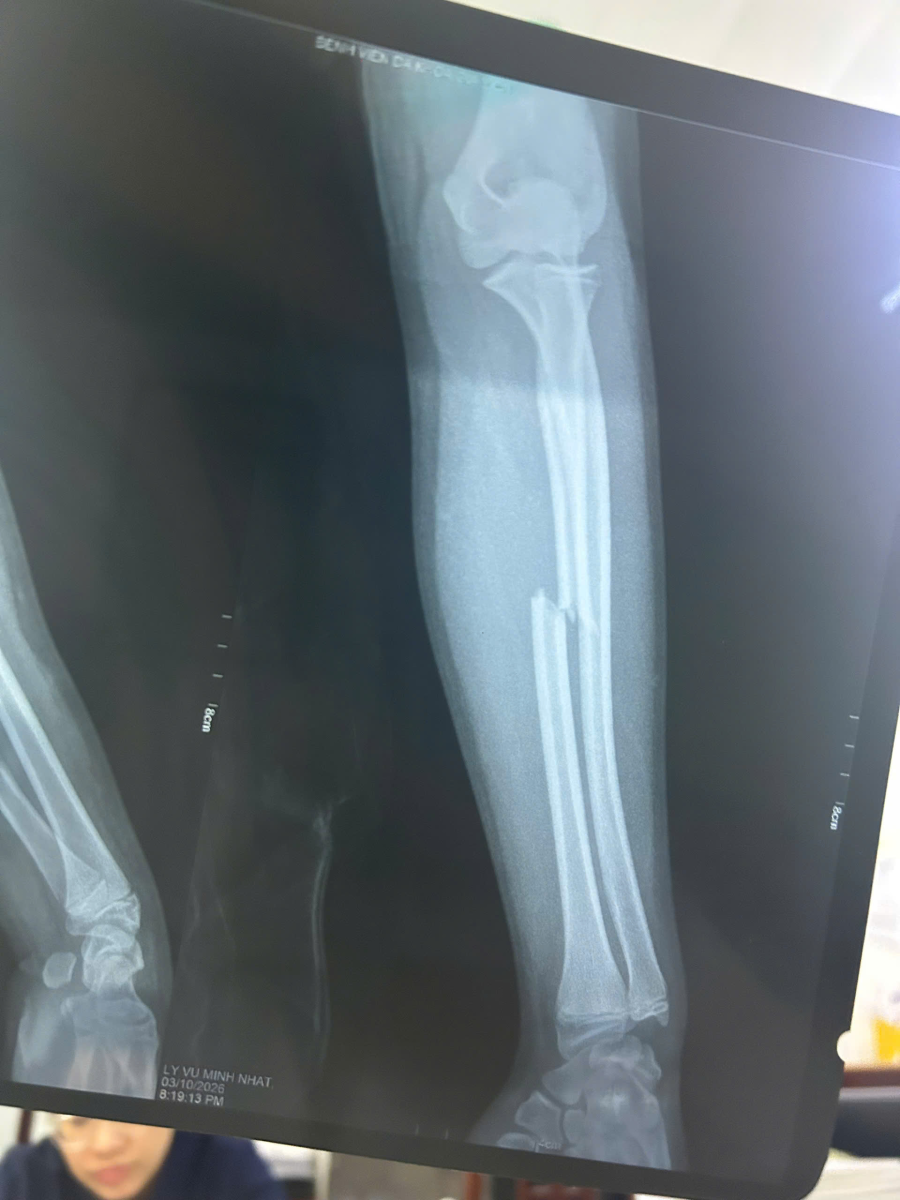

Qua thăm khám lâm sàng và kết quả chụp X-quang, các bác sĩ chẩn đoán bệnh nhân bị: Gãy kín 1/3 giữa xương quay tay Trái di lệch. Đây là vị trí gãy khó nắn chỉnh hoàn toàn bằng phương pháp bảo tồn (bó bột) thông thường do sự co kéo của các nhóm cơ vùng cẳng tay.

Ảnh 1: Ảnh X-quang trước mổ (ghi chú: Gãy di lệch 1/3 giữa xương quay).